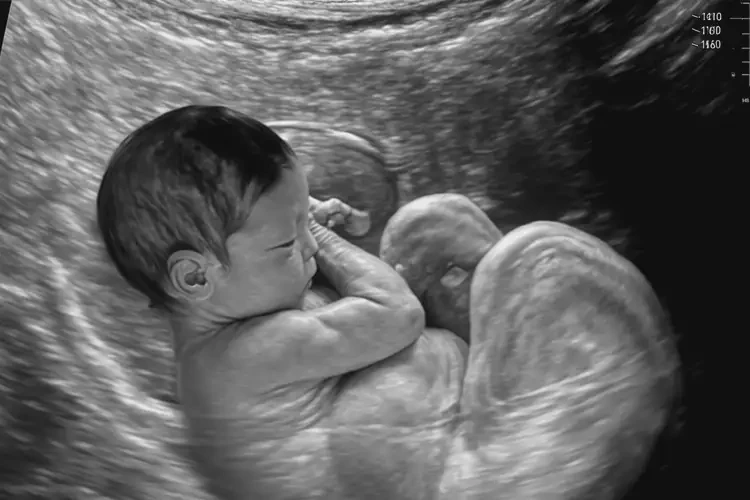

孕23周1天胎心率92有危险吗(图1)

• 超声检查:通过超声检查评估胎儿的发育情况、胎盘功能以及脐带情况。

孕23周1天胎心率92有危险吗(图2)